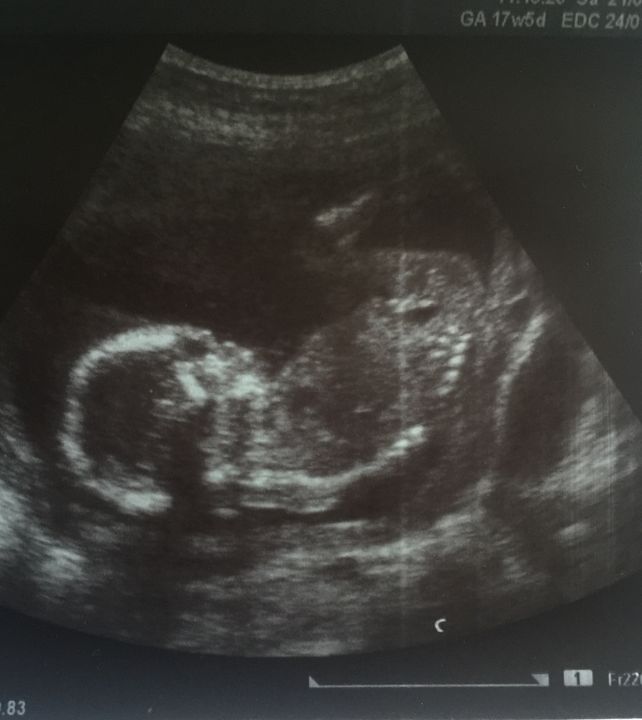

Интрига с полом продолжается) 17 недель +5 дней

УЗИ, КТГ, доплерСегодня было экспертное УЗИ + 2 скрининг. Проверяли как повлиял метипред и аутоиммунный процесс на малышика. Перед УЗИ очень переживала, почты всю ночь не спала. Но все оказалось хорошо - идем в срок, все показатели в норме, по органам тоже все ок ) По крови, естественно, результатов еще нет, но думаю там тоже не должно быть ничего страшного.

Очень надеялась, что сегодня мне наконец-то объявят пол. Но не тут то было))) Во-первых, малышик никак не хотел повернуться нужным местом, а только деловито отставлял в монитор попу: "Имел я ваше любопытство в виду" )). А когда таки мимолетно поворачивался - между ног оказывалась пуповина 😅 Врач не взялась гадать да и мучать меня попытками поймать нужный ракурс - и так уже возюкала по животу 20 минут. В общем, жить мне в интриге еще 4 недели - до следующего планового узи. Прям уж не знаю как дотянуть, боюсь сорвусь и схожу на внеплановое 🤣